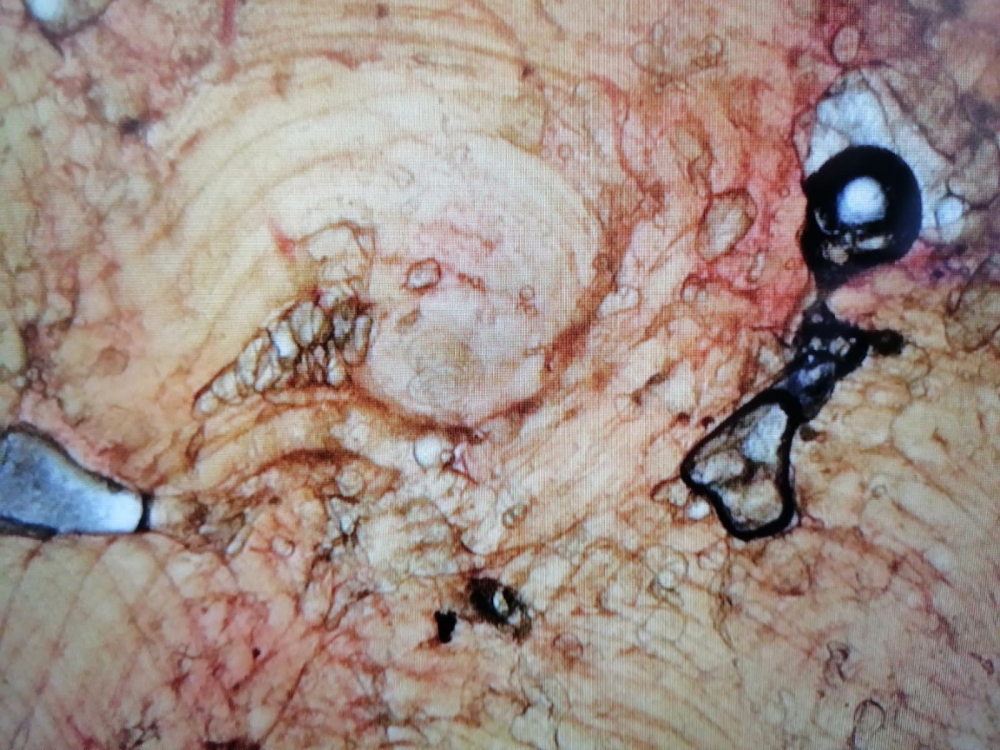

На фото личинки Trichinella spiralis в капсуле / фото: источник photogenica.ru, автор photowest